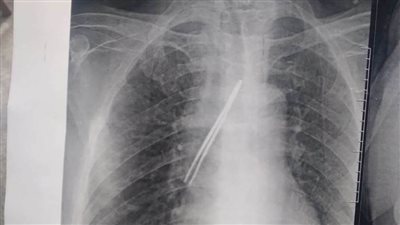

إنقاذ حياة فتاة ابتلعت "دبوس طرحة" بمستشفى بنها الجامعي

الثلاثاء 28/مارس/2023 - 03:50 م